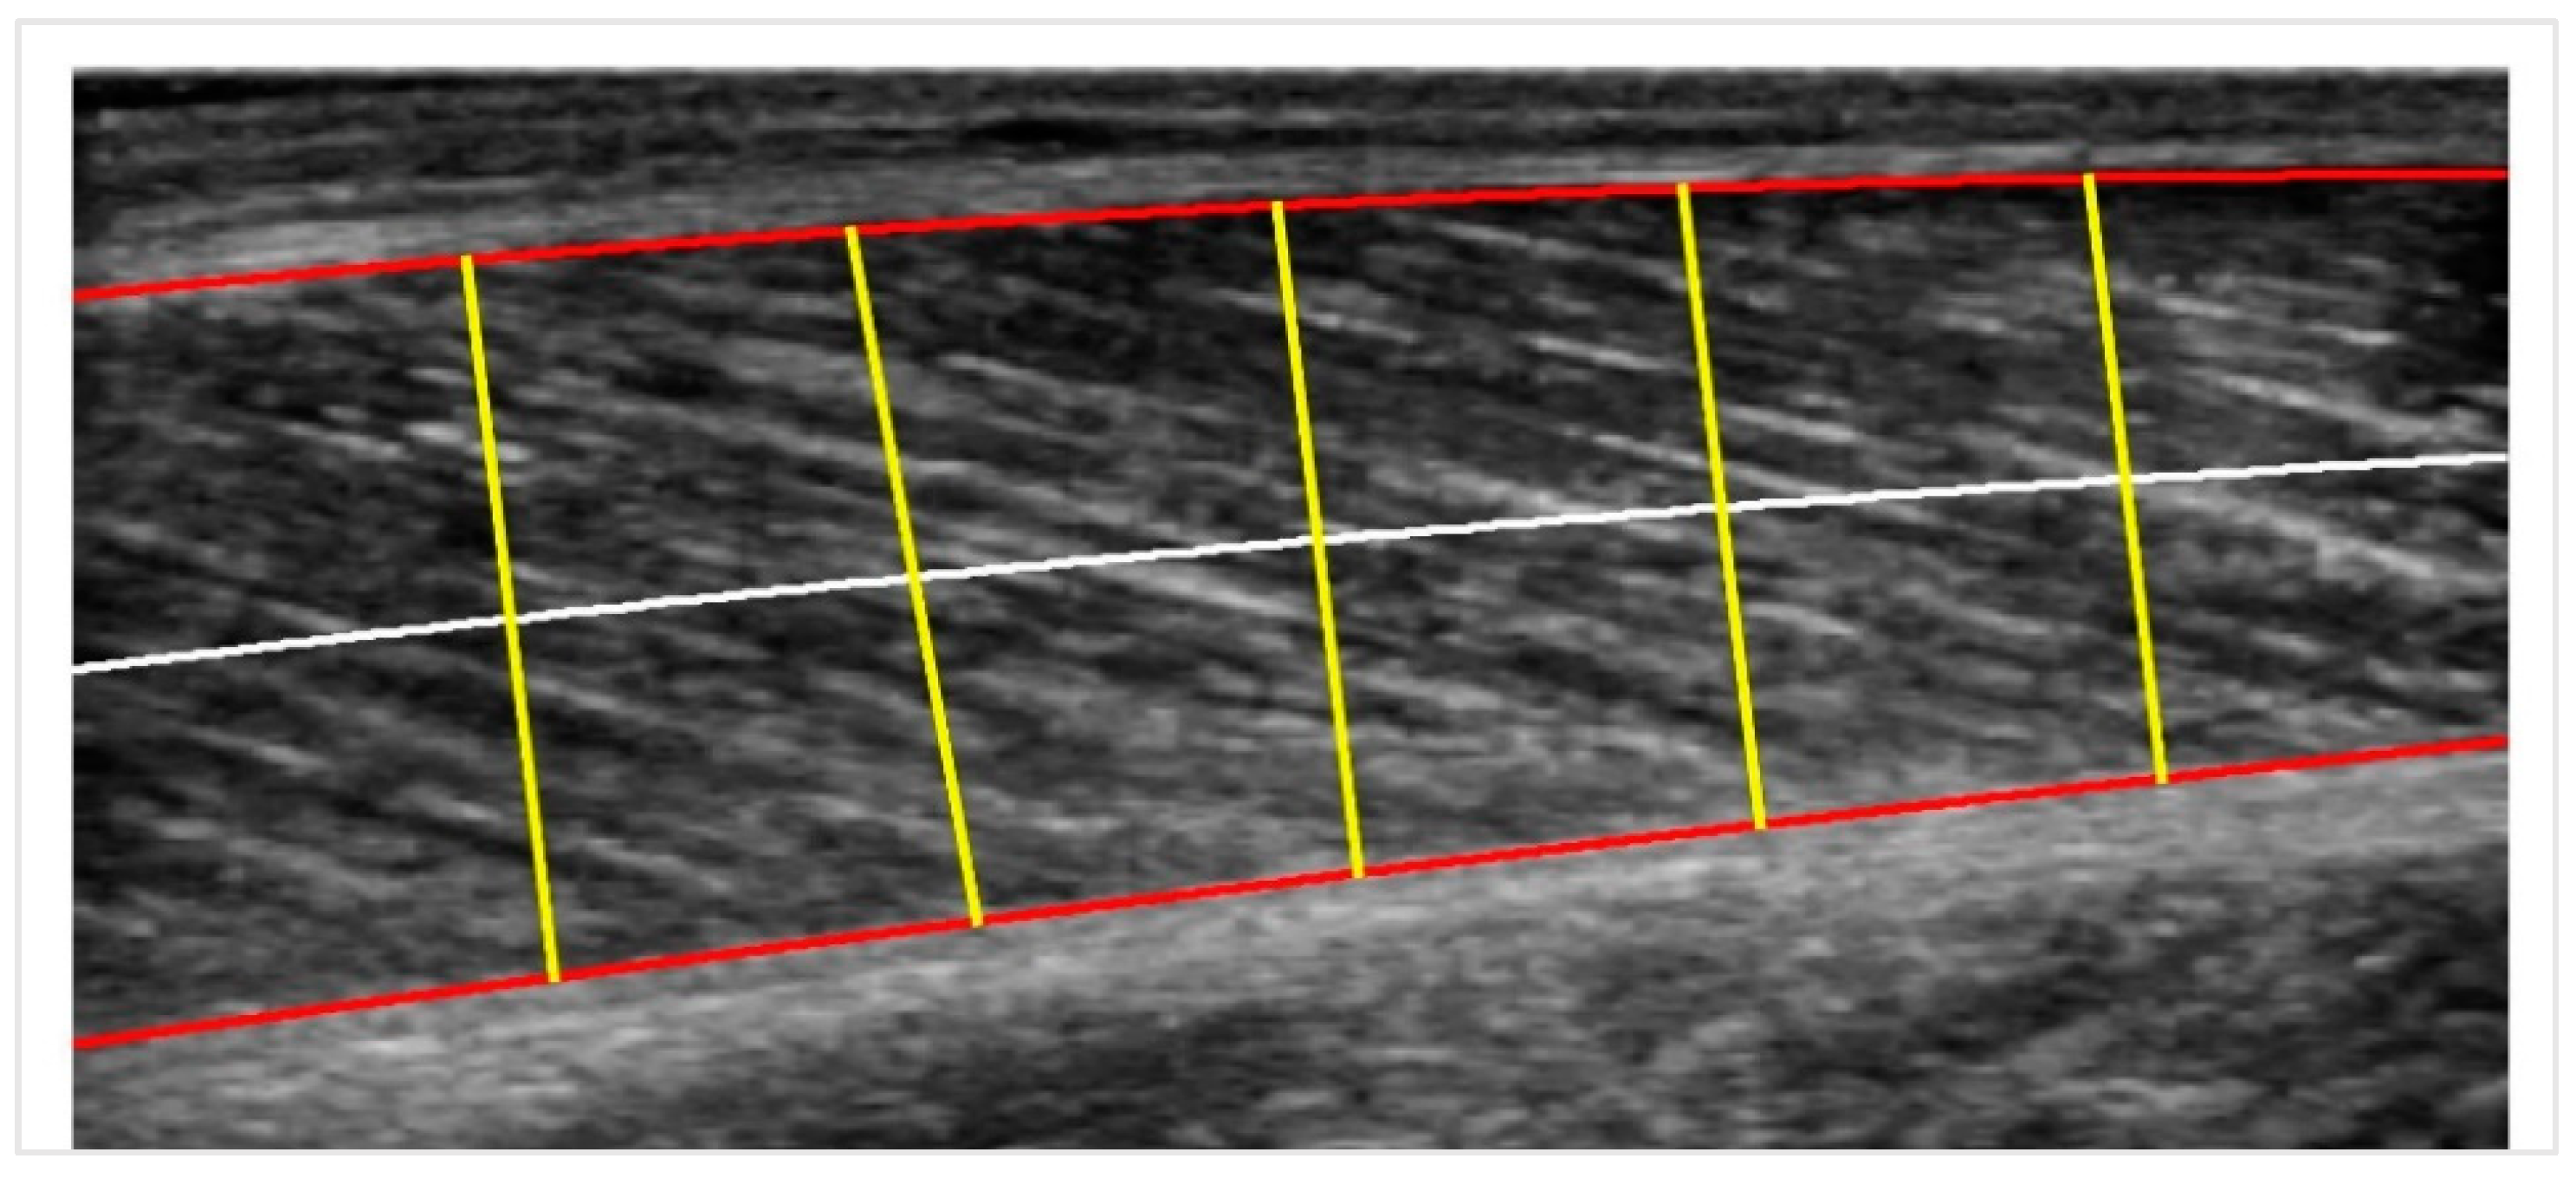

2.2. Muscle Thickness Calculation

2.2.2. Muscle Thickness Measurements